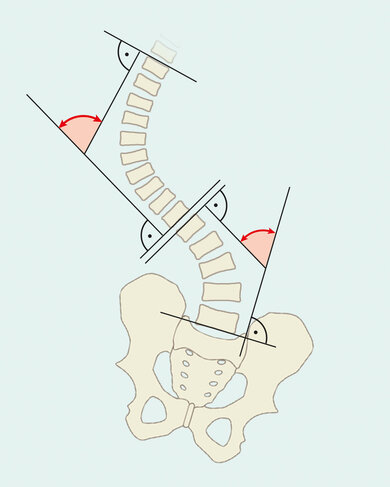

Eine Skoliose ist eine dreidimensionale Verkrümmung der Wirbelsäule. Die Krümmung in der Frontalansicht beträgt dabei laut Definition mehr als 10 Grad nach Cobb (siehe unten). Zusätzlich findet sich eine Rotation der Wirbelkörper, welche unterschiedlich stark ausgeprägt sein kann.

4. Nach der Art der Verformung

- C-förmig

- S-förmig

- Doppel-S-förmig (triplebogige-Skoliose)